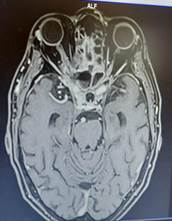

La resonancia magnética cerebral y de órbita mostró un engrosamiento del nervio ocular derecho y de su vaina nerviosa y signos inflamatorios de la grasa adyacente. Estos cambios se extienden hasta casi alcanzar el quiasma óptico. Ocupación casi completa de la luz de las celdillas etmoidales posteriores, del seno esfenoidal (Figura 1).

El paciente no se conocía diabético, debutó la enfermedad a los 65 años, fue tratado con hidratación parenteral, insulina regular con estabilización de la glicemia y recuperación del estado general. Por la protrusión ocular con parálisis del tercer par del ojo derecho se solicitó una resonancia magnética cerebral y de órbita, donde se observó un engrosamiento del nervio ocular derecho y de su vaina nerviosa y signos inflamatorios de la grasa adyacente. Estos cambios se extienden hasta casi alcanzar el quiasma óptico. También se observó una ocupación casi completa de la luz de las celdillas etmoidales posteriores, del seno esfenoidal. En los senos paranasales se observó un engrosamiento mucoso con nivel hidro-aéreo a nivel del seno maxilar izquierdo. Se inició antibióticos de amplio espectro por la sinusopatia. También al paciente se le realizó un tratamiento quirúrgico de la lesión retro orbitaria para diagnóstico y tratamiento, el examen directo de la lesión mostró hifas hialinas cenocíticas compatibles con mucorales, se inició anfotericina B que actualmente se encuentra recibiendo, con buena tolerancia.